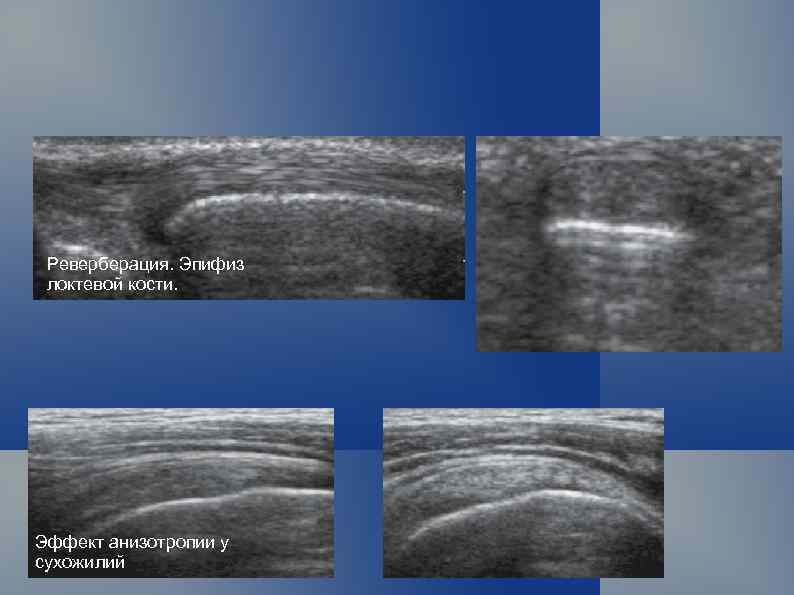

Реверберация. Эпифиз локтевой кости. Эффект анизотропии у сухожилий